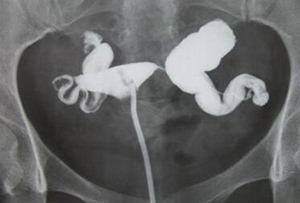

输卵管积水是指输卵管炎后,因粘连闭锁,或白细胞长期侵润导致输卵管间质水肿、渗出,输卵管粘膜上皮脱落,没能得到及时有效治疗形成水样液体,也有的液体被吸收剩下一个空壳,造影时显示出积水影。

输卵管积水图

输卵管积水造影图片

目前输卵管积水检查金标准是输卵管造影,广州圣丹福医院采用“皇家5E超声成像输卵管显影术”,10-20分钟即可明确输卵管积水具体部位。“皇家5E超声成像输卵管显影术”不同于其它医院的碘油造影,而是采用可吸收、的碘水造影,对输卵管没有损伤。造影后如果其它的生育条件具备,造影后当月就可以在医生的指导下试孕。